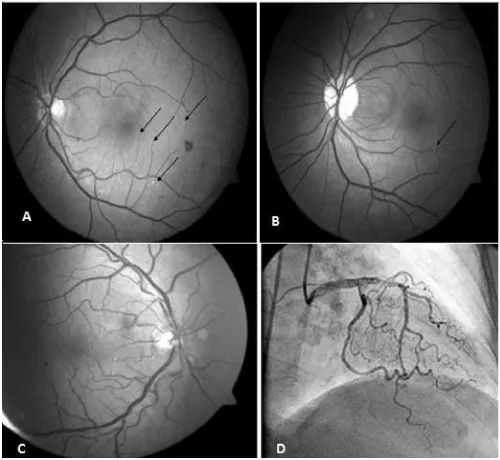

Drusenoid bodies were found in 53 patients (Figure 1A). Retinal vein occlusion (RVO) was found in 10 patients (5 women, 5 men) and retinal collateral vessel formation was observed in 11 patients. Both collateral vessel formation and presence of RVO were found in 9 of these patients. Hollenhorst plaque was found in three patients (Figure 1B).  Increased retinal tortuosity was found in 65% of the patients (Figure 1C). The frequency of RVO was statistically significantly higher in patients who were not using ASA (26,3%) compared to the patients who were using ASA (6,2%) and retinal collateral vessel formation was observed with a statistically significantly higher rate in patients who were not using ASA compared to the patients who were using ASA  (p<0.001). Among fundoscopic findings, drusenoid bodies were found with a significantly higher rate in patients who were smokers (p<0.001). Similarly, drusenoid bodies were found with a statistically significantly higher rate in patients who were not using clopidogrel compared to the patients who were using clopidogrel (p<0.001).

Figure 1: A: Drusenoid Bodies (indicated with black arrows), B: Hollenhorst plaque (black arrow), C: Retinal vascular tortuosity, D: Coronary vascular tortuosity.

Point opacities were observed on the retinal surface in 52% of our patients. When funduc camare was used, it was thought that these opacities were drusenoid bodies (Figure 1A). It was thought that the drusenoid bodies which were found with a high rate in our study might be small drusens related with age-related macula degeneration (ARMD) and/or particles located in the retina by way of extravasation of intravascular cholesterol crystals. ARMD is the most common legal cause of blindness in the population aged 65 years and older [12]. In all studies, the prevalence of ARMD has shown an increase with age. Atherosclerosis in the carotid vascular bed, presence of systemic hypertension, smoking and dislipidemia are risk factors for development of ARMD [13,14]. Similarly, drusenoid bodies were found with a statistically significantly higher rate in patients who were smokers in our study.

As known, increased tortuosity in the arteries occurs as a result of aging or pathological changes in vascular elastic material [17-20; Figure 1D]. It has been reported that atherosclerosis, hypertension and aging play a role in development of arterial tortuosity [21-23]. Increased tortuosity in the retinal arteries occurs as a result of aging or pathological chenges in vascular elastic material [24,25]. Increased tortuosity may also be observed in the retinal arteries. It is known that this is observed frequently especially in retin al pathologies including diabetic retinopathy, retinal vein occlusion and retinal vasculitis. In a study conducted by Owen et al., a relationship was shown between increased cholesterol (especially increased triglyceride level) and blood pressure (risk factors for coronary artery disease) in the first 10 years of the childhood and tortuosity in the retinal arteries [26]. Presence of retinal tortuosity in 65 of 100 patients with coronary artery disease in our study supports this study.